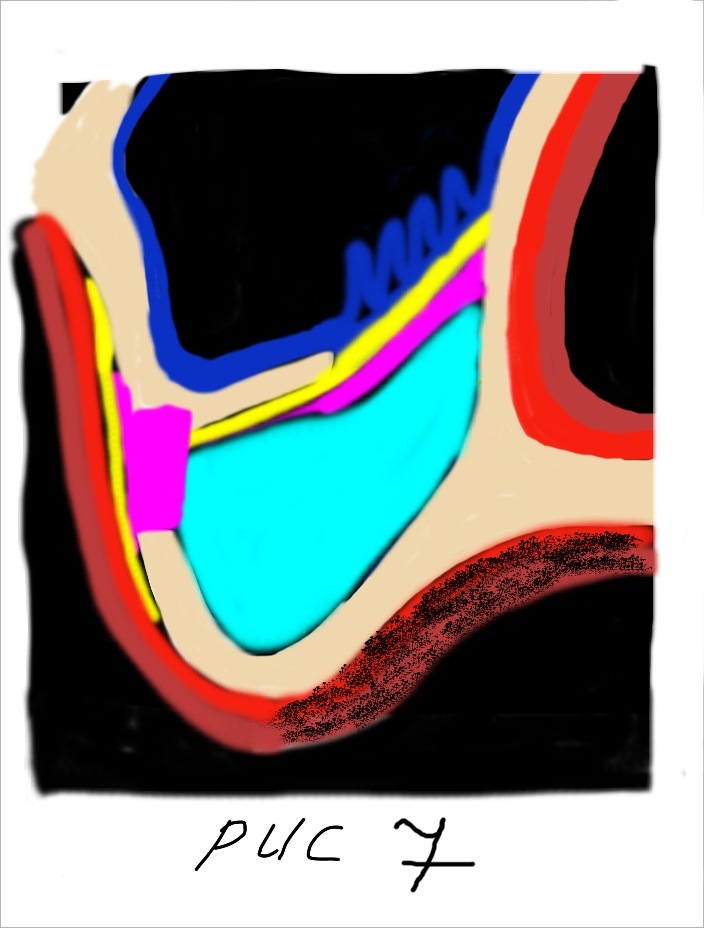

... с последующим покрытием коллагеновой мембраной Биоматрикс (рис 7).

... с последующим покрытием коллагеновой мембраной Биоматрикс (рис 7).